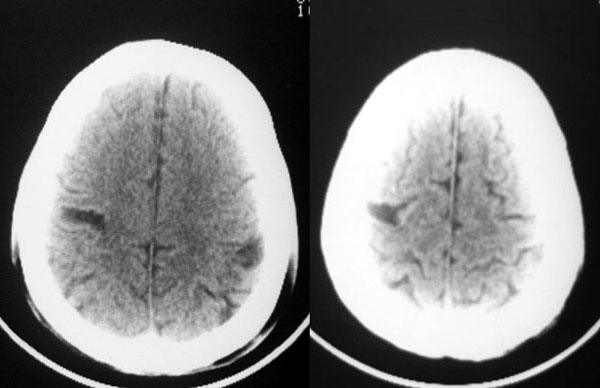

以下是引用dyqct在2006-11-9 15:04:00的发言:[br]左枕叶、双顶叶各见一处似三角形低密度区,边界尚清楚,无占位效应,累及皮质,白质侧未见灰质影。余所见未见异常。[br]考虑:1、脑软化灶;[br] 2、不支持脑裂畸形,该病病变区两侧应有灰质带——即灰质异位,临床上常有顽固性颠痫。当然了脑软化灶也偶会出现颠痫。

以下是引用守望可可西里在2006-11-9 15:06:00的发言:[br][br] 1.左侧枕叶低密度与侧脑室相通,考虑开唇型脑裂畸形。[br] 2.双侧顶叶低密度考虑局部脑沟异常扩大,发育问题。